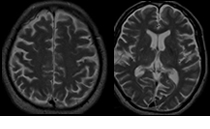

脳卒中とは脳の血管が閉塞(脳梗塞)あるいは破裂(脳出血、くも膜下出血)した結果、脳の働きが損なわれる病気です。脳卒中は単一臓器の死因としても多く、代表的な国民病です。

脳血管自体の動脈硬化や血栓形成の結果として脳血管が閉塞する脳血栓症と脳以外で形成された血栓などが脳血管を閉塞する脳塞栓症に分けられます。 -

脳出血の約80%は高血圧性ですが、一部は脳血管奇形や血液凝固異常などに起因します。 -

脳動脈瘤が破裂して、激しい頭痛や意識障害で突然発症する怖い病気です。特に再破裂、脳血管の攣縮(痙攣)による脳梗塞、水頭症を合併すると重篤になります。